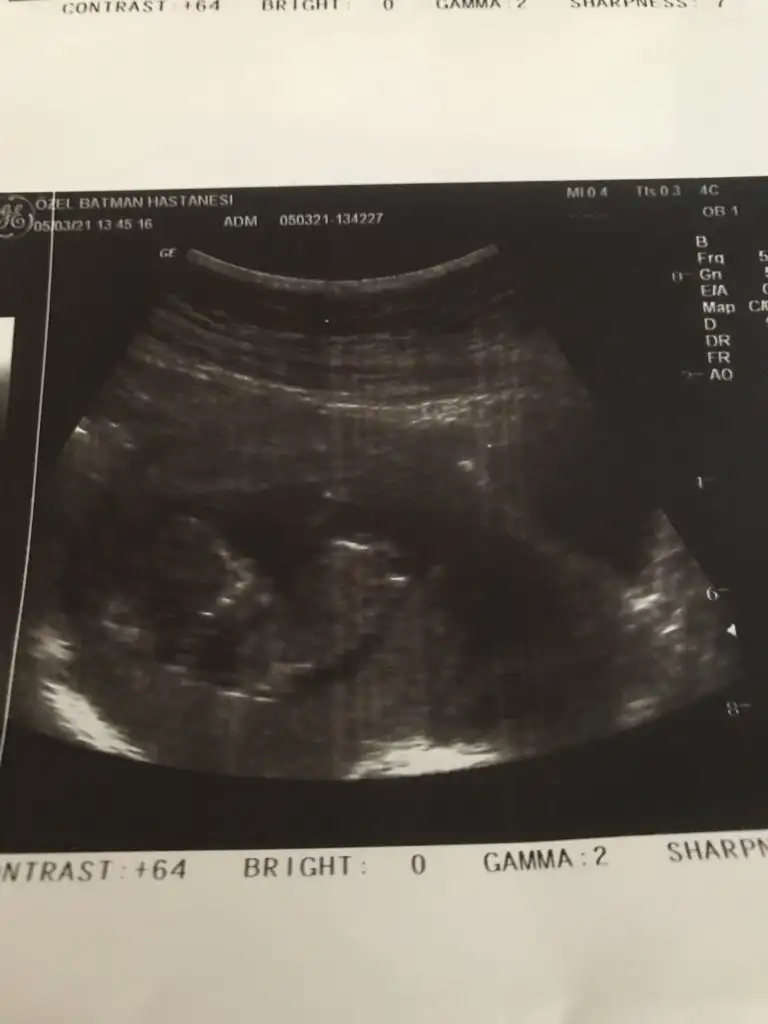

Karından 6+5 bakabilir misiniz acaba🧡